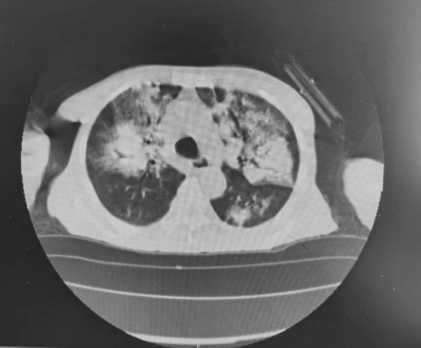

根据检查结果,医生诊断老人为“休克、急性肾损伤3期、高钾血症、心功能不全、重度贫血、支气管扩张、胸腔积液”。

老人在急诊的肺部CT

病因是原发病恶化还是肺部感染呢?我们再次进行纤维支气管镜检查,肺泡灌洗液基因测序显示深部浸润真菌感染为白色念珠菌,肺部CT显示双下肺存在大面积肺不张。为了解决肺部感染这一目前首要问题,医生给予老人联合足量抗生素治疗,同时采用了更强有力治疗措施,即俯卧位通气。